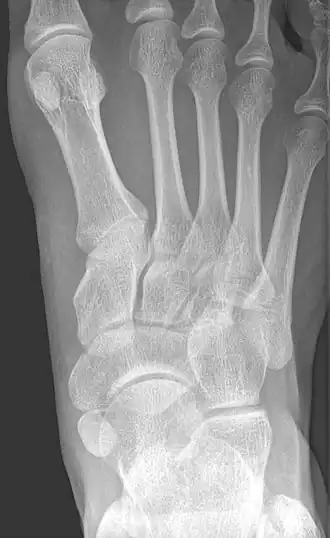

X-ray of the foot showing an accessory navicular bone

An accessory navicular bone is an accessory bone of the foot that occasionally develops abnormally in front of the ankle towards the inside of the foot. This bone may be present in approximately 2-14% of the general population and is usually asymptomatic.[1][2][3] When it is symptomatic, surgery may be necessary.